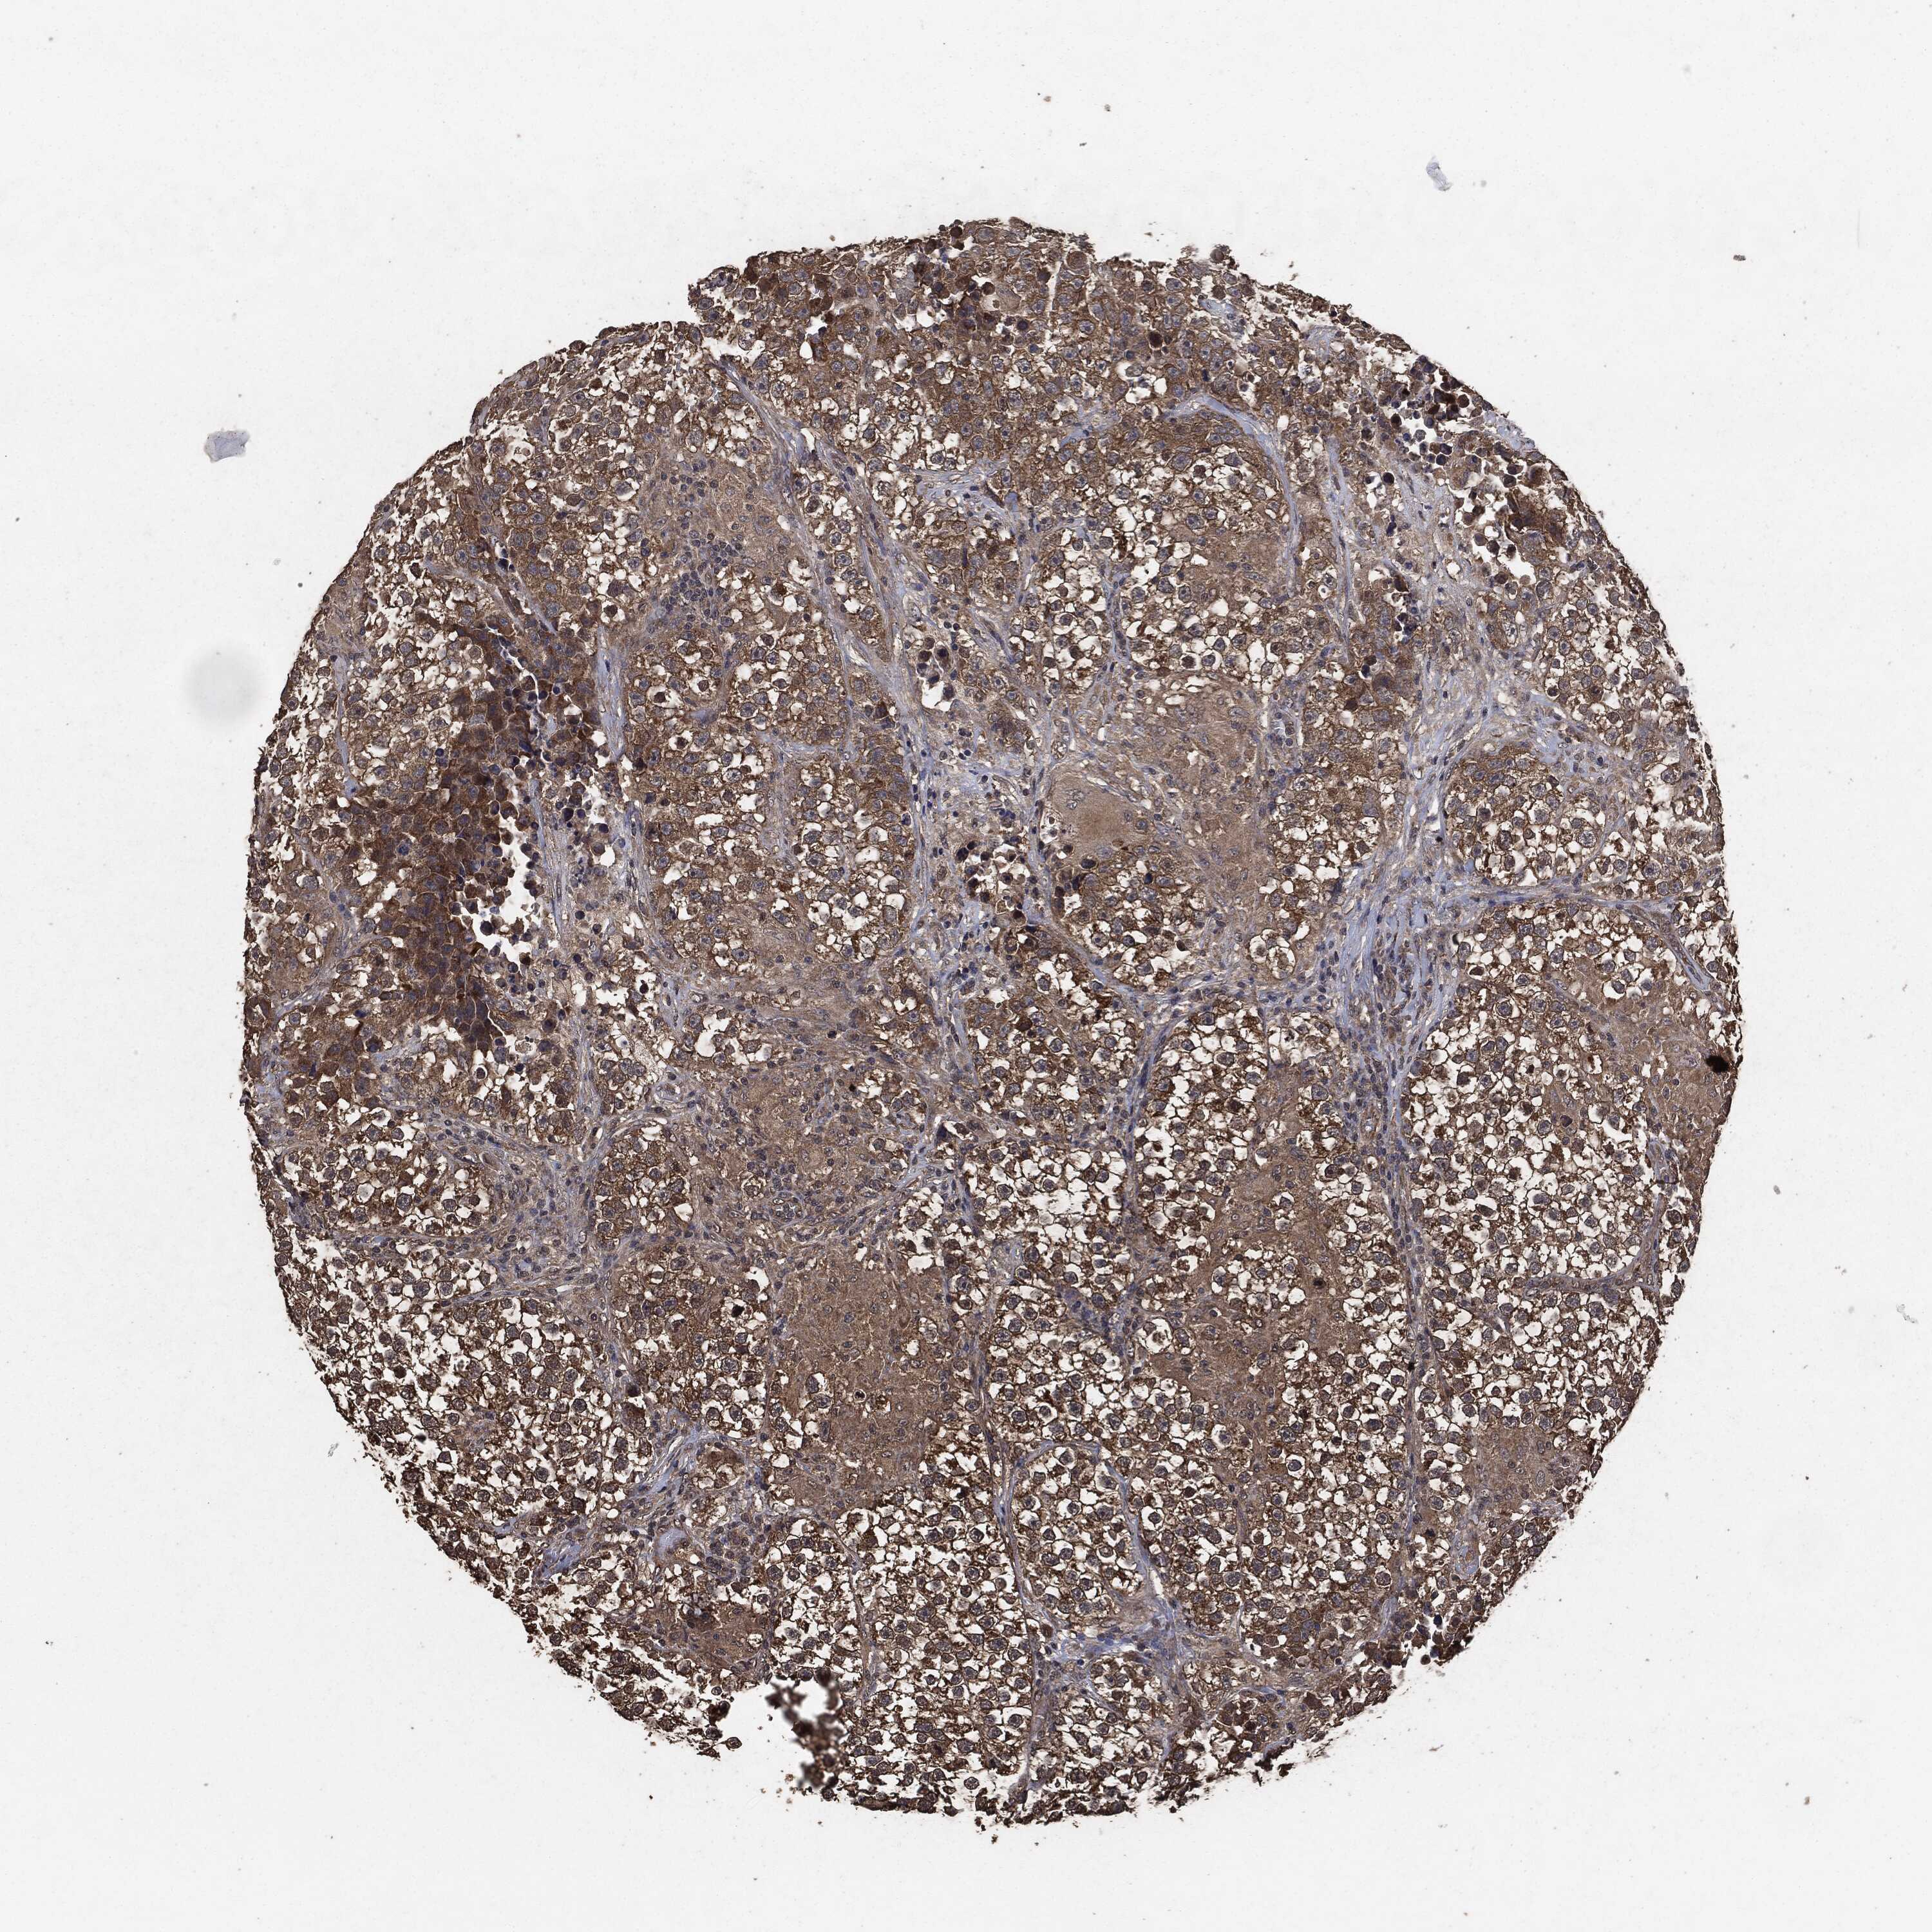

TESTIS CANCER - Protein expressioni

A mouse-over function shows sample information and annotation data. Click on an image to view it in a full screen mode. Samples can be filtered based on level of antibody staining by selecting one or several of the following categories: high, medium, low and not detected. The assay and annotation is described here.

Note that samples used for immunohistochemistry by the Human Protein Atlas do not correspond to samples in the TCGA dataset.

Antibody stainingi

Antibody staining in the annotated cell types in the current human tissue is reported as not detected, low, medium, or high, based on conventional immunohistochemistry profiling in selected tissues. This score is based on the combination of the staining intensity and fraction of stained cells.

Each image is clickable and will lead to virtual microscopy that enables deeper exploration of all samples and also displays staining intensity scores, fraction scores and subcellular localization as well as patient and tissue information for each sample.

Antibody HPA064427

Antibody HPA075510

Antibody CAB021903

Carcinoma, Embryonal, NOS